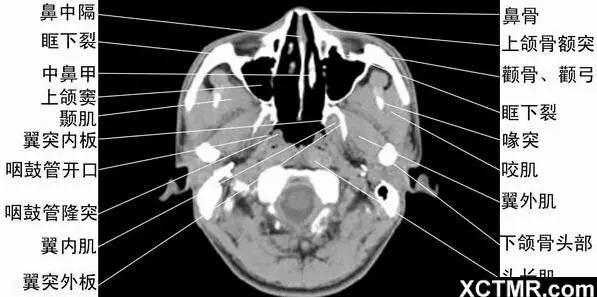

8CT軸位鼻腔和鼻竇層面(中鼻甲水平) - 解剖圖片